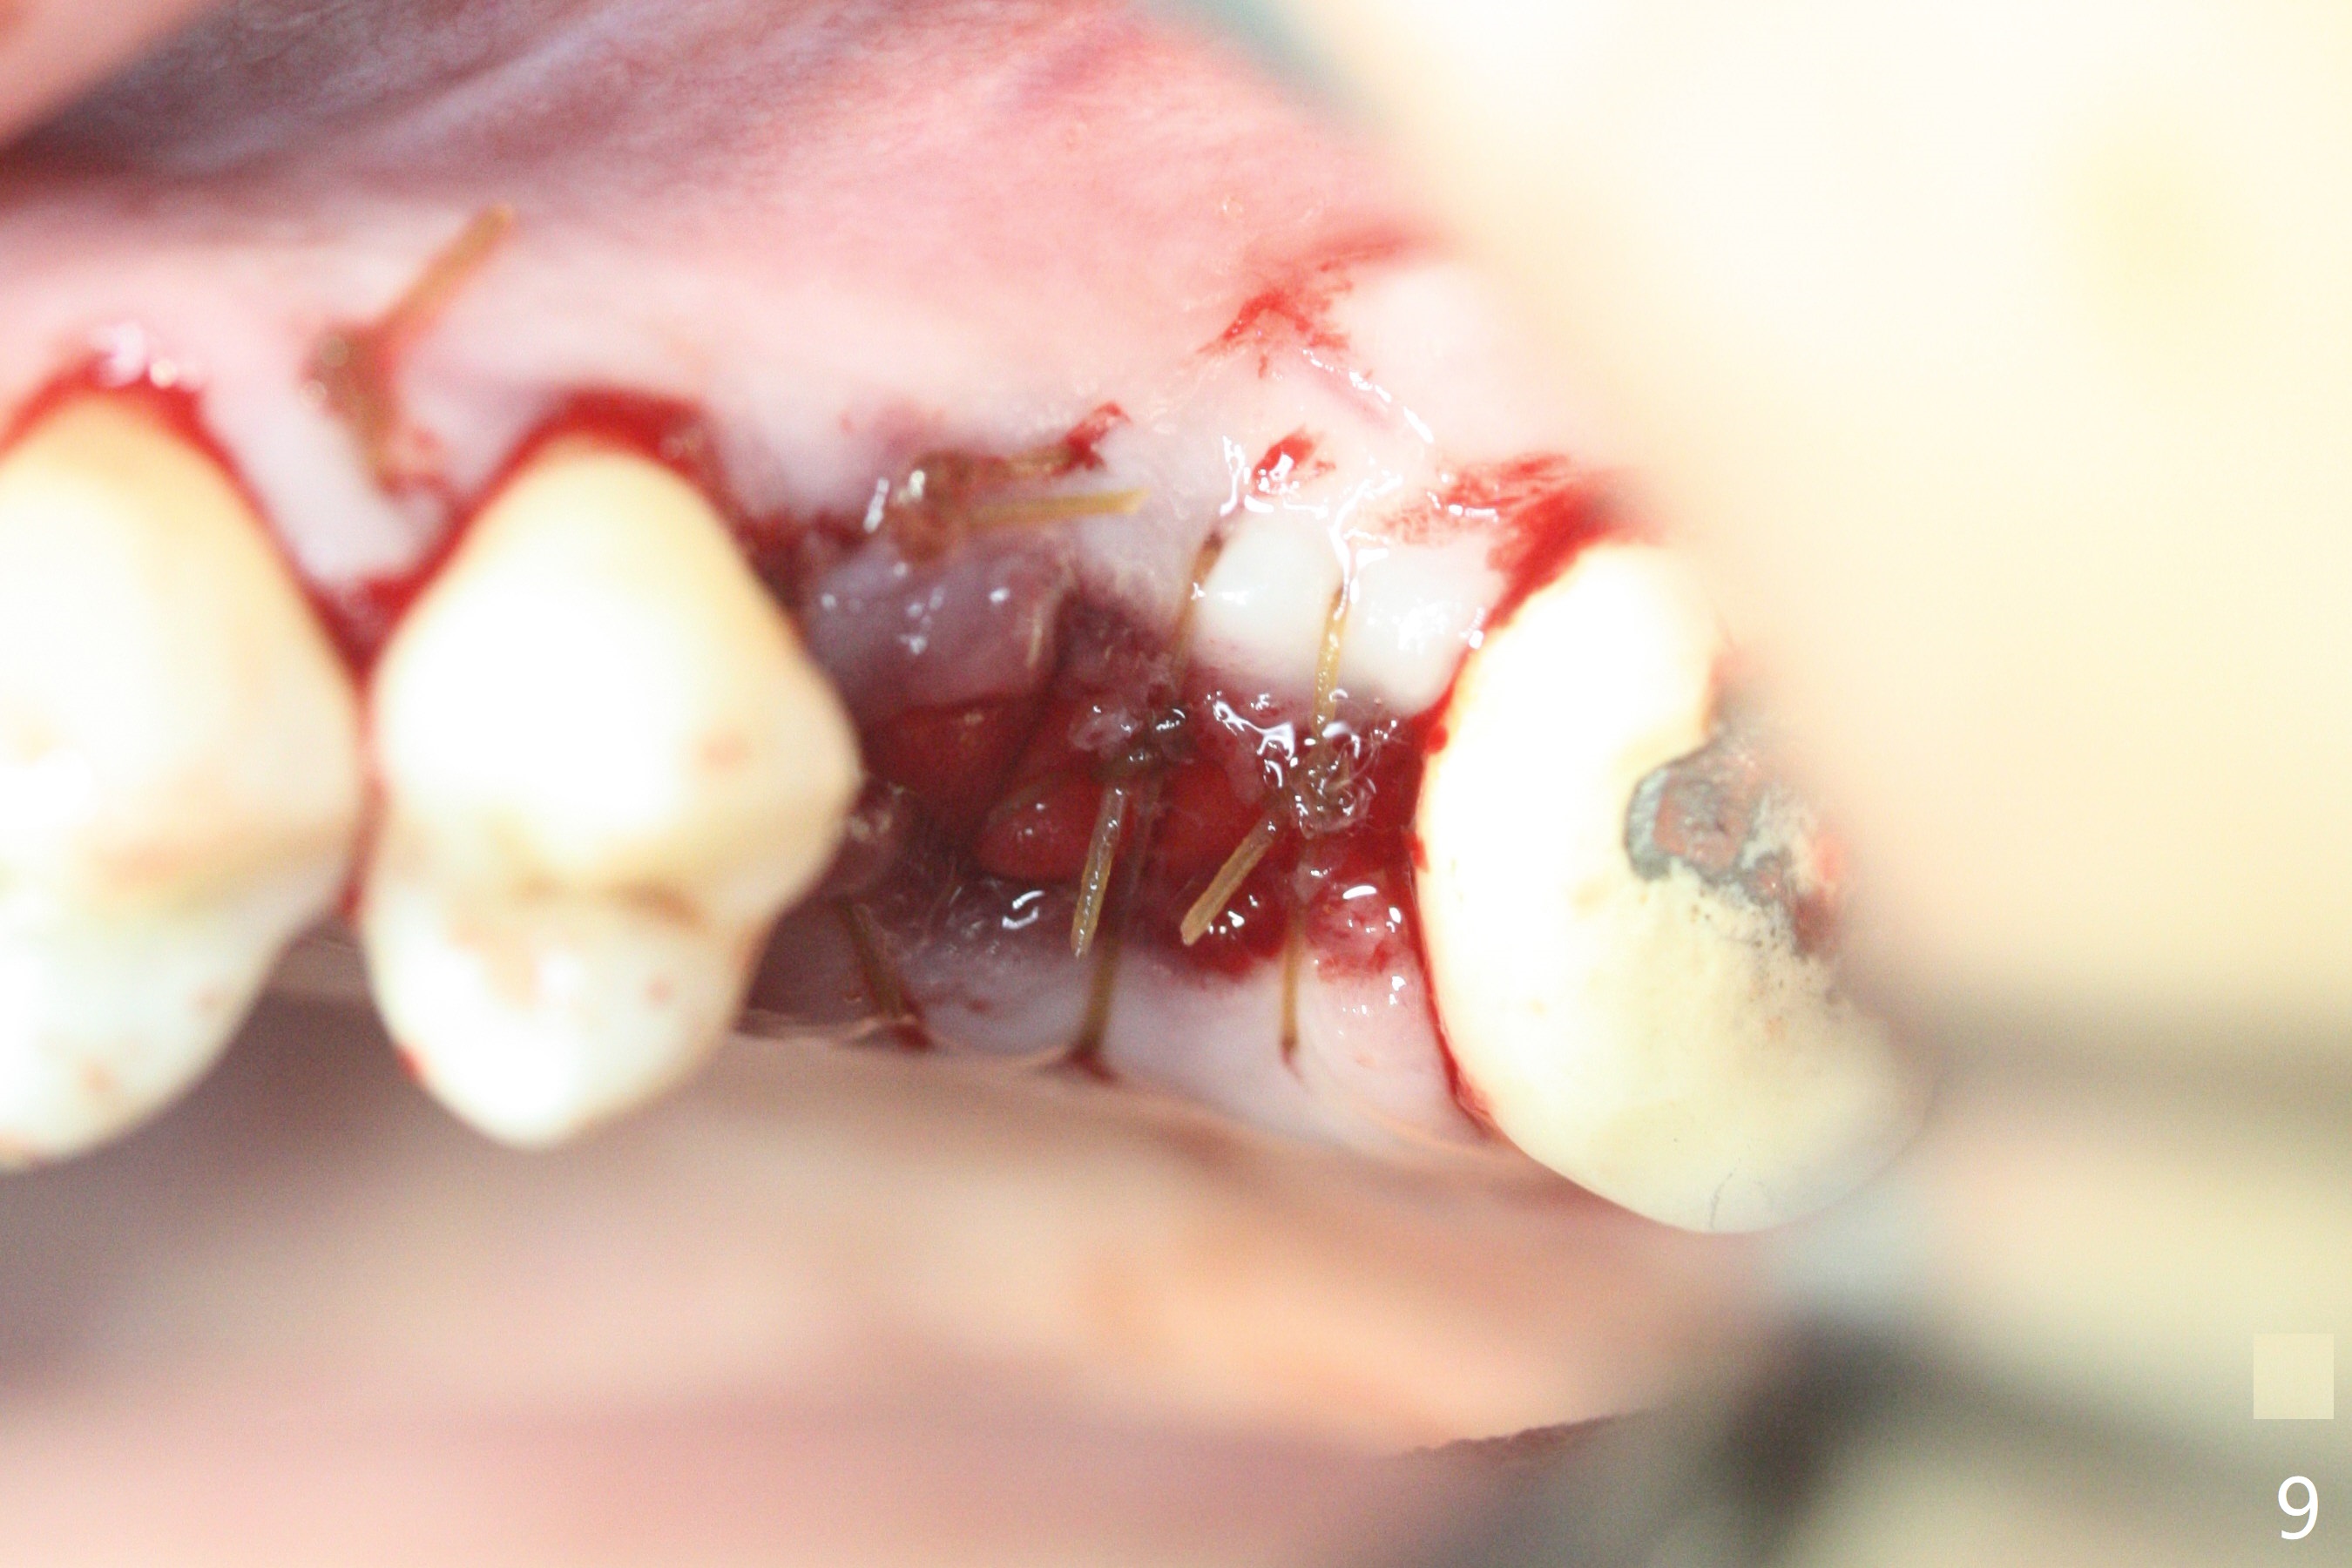

A 57-year-old woman complains of bad smell while use of water flosser between 11 and 21 months post cementation of implant crown at #14 (Fig.1,2). Bone loss is more obvious with CBCT (Fig.3,4), in spite of apparently normal gingiva around the implant after removal of the abutment and crown (Fig.5). In fact the buccal (B) gingiva is fragile with easy access to the underlying implant plateau. Following flap elevation, the bone loss is evident (Fig.6), but the implant plateau is slightly subcrestal (Fig.7 *). The exposed implant threads are covered with the 1st round of bone graft (Fig.8). After 2nd round of allograft (Fig.10-12) and collagen membrane, the flaps are approximated (Fig.9). The wound is covered by acrylic dressing. The latter is loose, but stays in place 1 week postop (Fig.13). Due to short neighboring teeth, the acrylic dressing is able to be removed with wiggling; it appears that the wound is healing (Fig.14). The dressing returns for another 2 weeks; some of the graft has been lost (Fig.15). The dressing does not return 7 weeks postop, since the wound is healing (Fig.16).